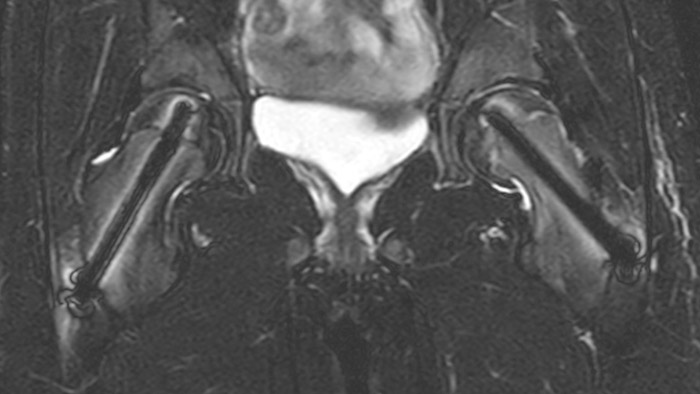

Slipped capital femoral epiphysis

After intervention with two cannulated titan screws, it is important to check that the circumference is normal and without necrosis. The screws can cause major metal artifacts, but O-MAR allows to improve visualization of tissue and bone in the near vicinity of MR Conditional orthopedic implants1.

1 Only for use with MR Safe or MR Conditional implants by strictly following the Instructions for Use